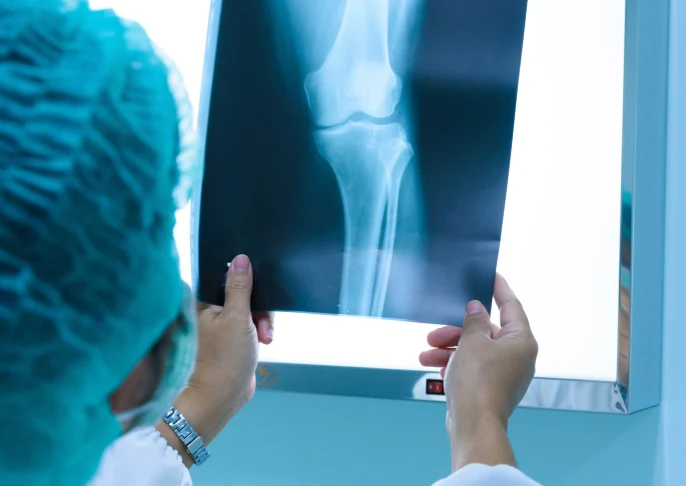

X-ray technology uses ionizing radiation to create images of bones and soft tissues. These may appear as shades of gray on X-ray film or digital film. Doctors recommend this procedure to better diagnose fractures, pneumonia, and other conditions.

With the help of our state-of-the-art portable digital X-ray equipment, our experts perform basic radiology exams and procedures, helping you diagnose your condition and offering radiologically guided solutions, like joint injections.

Your doctor will recommend that you go for an X-ray test. It is used to see the conditions of the bones and other joints. Apart from this, an X-ray procedure is also helpful to identify issues affecting soft tissue and internal organs. Patients with the possibility of conditions such as bone fractures, tooth problems, and so on are advised to have an X-ray examination.